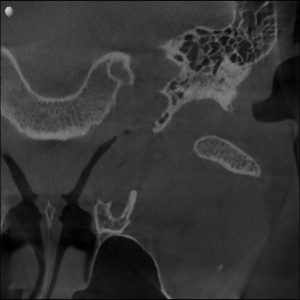

MRI confirmed bilateral disc displacement without reduction — both jaw joints had discs that had slipped out of position, causing compression and inflammation.

Clinical & Radiographic Findings

- Bilateral disc displacement without reduction

- Restricted opening (31 mm → improved to 47 mm)

- Myofascial tenderness and deep bite

- Significant parafunctional clenching pattern

Bilateral TMJ dysfunction with disc displacement and muscular hyperactivity.